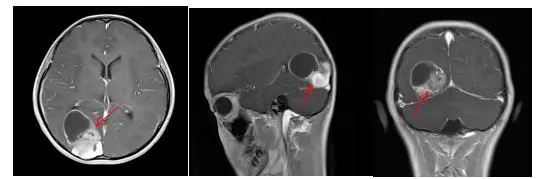

病史:患者近半月来频繁头痛,MRI检查:右侧枕叶、颞叶4.0*3.9*4.0cm囊实性占位,多考虑胚胎来源肿瘤。患者无发热,呕吐等情况,神经系统查体无明显阳性体征。

术前影像:右侧枕颞叶囊实性占位,边界清晰,囊壁及实性部分强化明显。

术前术后影像对比: